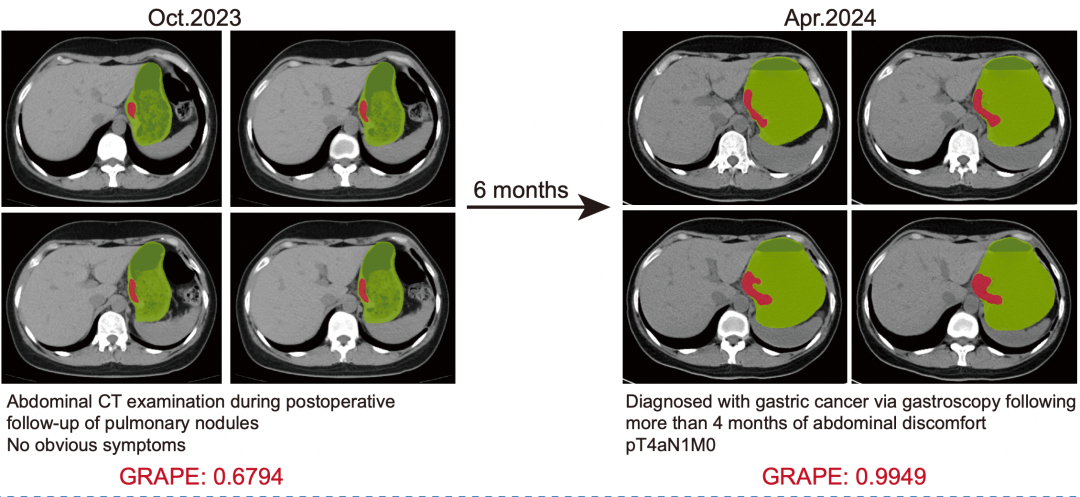

论文第一作者、浙江省肿瘤医院胃外科博士胡灿介绍,DAMO GRAPE模型有望填补在影像检查中机会性发现早期胃癌的空白。本次研究中,团队就对11名患者确诊胃癌前的CT影像进行回顾性分析,发现AI模型可提前2到10个月发现胃癌。例如,其中1名45岁患者因腹部不适接受胃镜检查,确诊局部晚期胃癌,而该患者6个月前因其他疾病做过胸腹部平扫CT检查,当时腹部未报告有病变。胡灿将片子导入AI模型,提示存在胃癌病灶。也就是说,如果6个月前就有AI自动监测,这名患者将在更早阶段确诊,不漏诊,另外可更早接受治疗。

AI提前6个月识别出胃癌